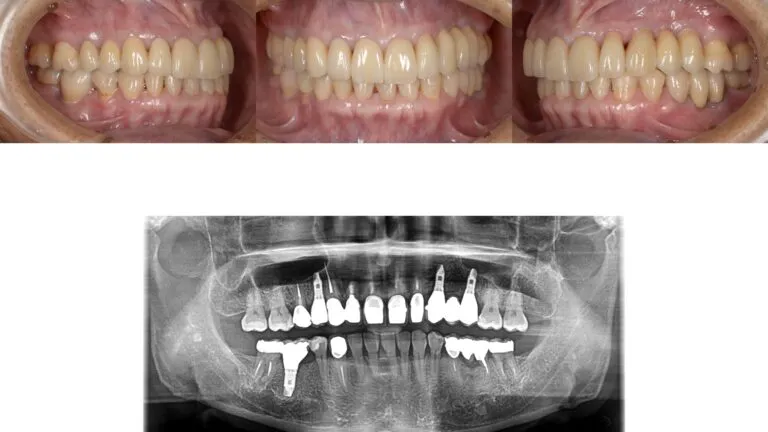

症例3

- 主訴

- 歯が揺れている。全体的な治療を希望

- 治療内容

- インプラント治療、セラミックによる補綴治療

- 治療費

- 450万

- 治療期間

- 1年6ヶ月

- 通院回数

- 50回

- 想定されたリスク

- 将来的な二次カリエス、歯周病の悪化

- コメント

- 入れ歯を使用せずに、しっかり噛めるようになりたいという希望を達成することができました。

before

after